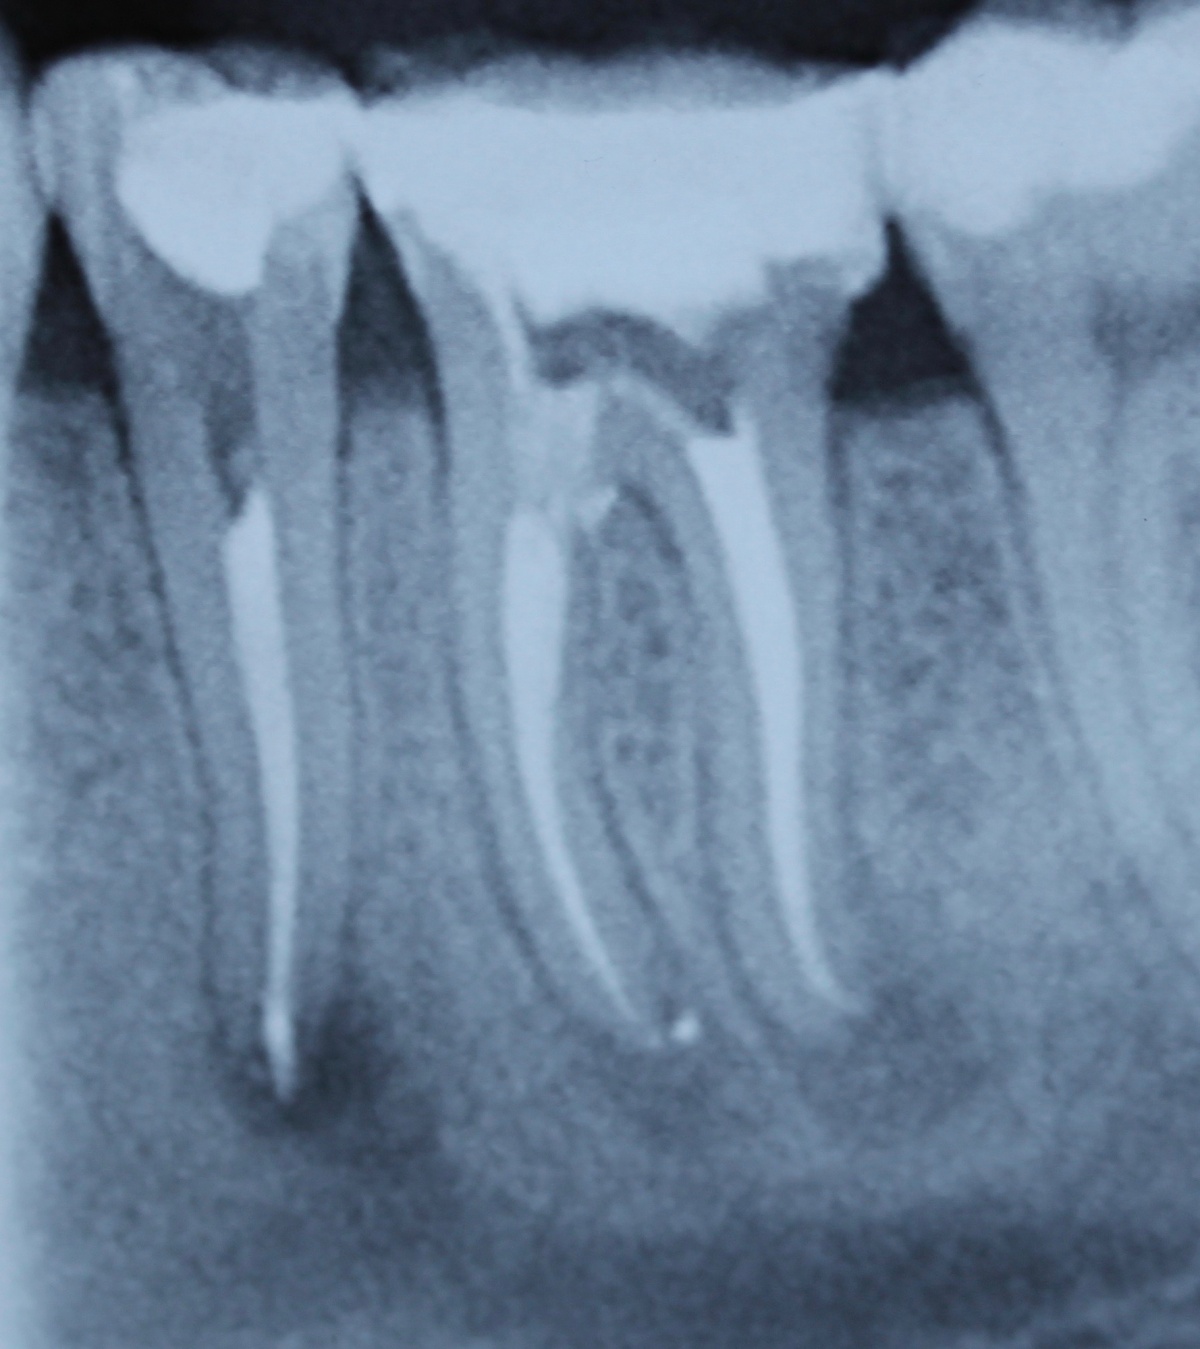

Dem Behandler kommt die Aufgabe zu, behandlungsbedingte Fehlerquellen möglichst auszuschalten. Eine solche kann die Ausdehnung der Trepanationsöffnung sein. Weitestgehend bekannt ist, dass ein gradliniger Zugang zu den Wurzelkanälen geschaffen werden sollte. Dieser technisch einfach umzusetzende Behandlungsschritt hilft den mechanischen „Stress“ durch Torsion auf die NiTi-Feilen deutlich zu verringern. Klinisch werden in nicht seltenen Fällen jedoch deutlich unterdimensionierte Trepanationsöffnungen oder persistierende Überhänge vorgefunden, welche die Belastung auf die Feilen unnötig erhöhen. Aufgrund stetig verbesserter technischer Möglichkeiten, wie beispielsweise die Anwendung hochauflösender Operationsmikroskope sowie der Ultraschalltechnologie, zieht heutzutage allerdings die Fraktur einer Feile selten die sofortige Extraktion nach sich. Sehr häufig ist die orthograde, bei ungünstiger Lage des Fragments seltener die retrograde, Entfernung möglich. Unter besonderen Voraussetzungen bei gleichzeitigem Abwägen des Risiko-/Nutzenverhältnisses ist auch das Belassen des separierten Instruments als praktikable Lösung möglich (Abb. 9 und 10).